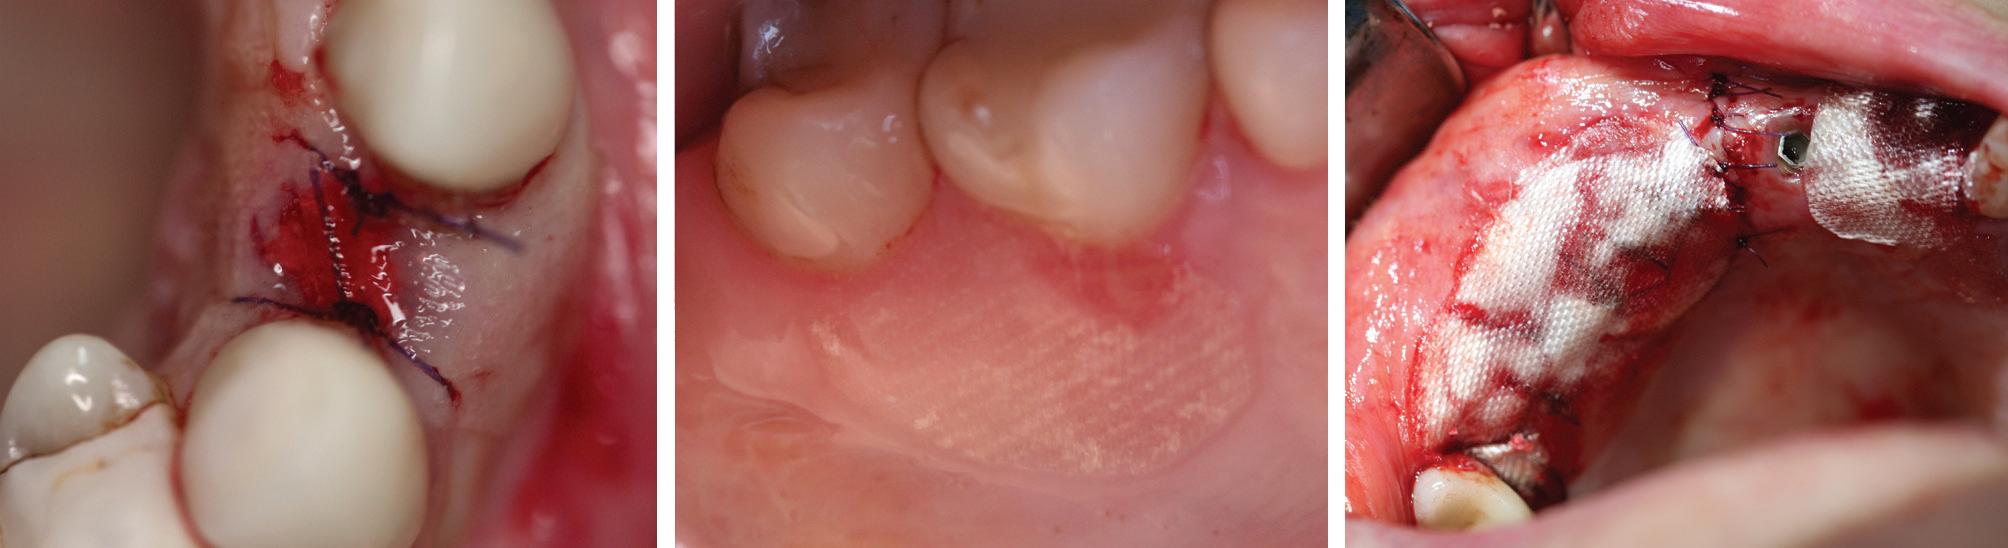

”I have been using the new Yxoss with a dense structure for the last 2 years and I can state that they are very effective and predictable devices for horizontal and vertical ridge augmentation. When associated with 70% of autogenous bone chips and 30% of DBBM their efficacy is comparable withthe one of traditional PTFE non-resorbable membranes, but much easier and faster to be installed.“

Prof. Massimo Simion

”I have been using the new Yxoss with a dense structure for the last 2 years and I can state that they are very effective and predictable devices horizontal and vertical ridge augmentation. When associated with 70% of autogenous bone chips and 30% of DBBM their efficacy is comparable withthe one of traditional PTFE non-resorbable membranes, but much easier and faster to be installed.